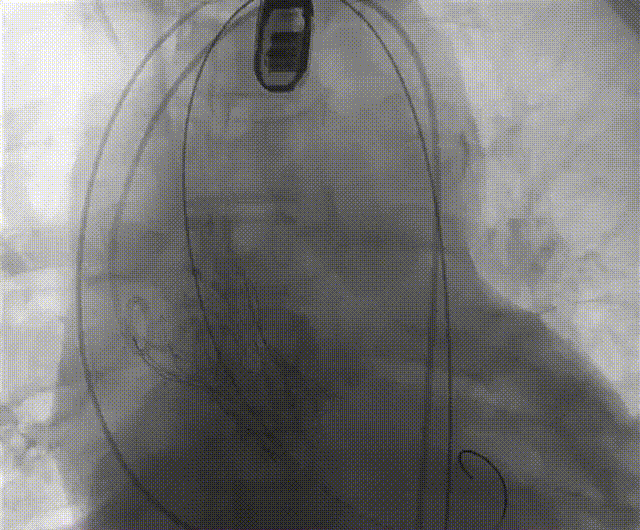

手术流程概括

零位定位开始释放,一次释放,零位释放位置良好,决定完全释放。

释放后多体位观察造影,瓣膜位置良好,展开良好,轻微瓣周漏。